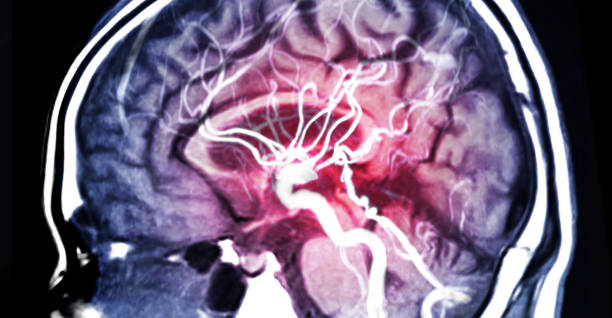

뇌출혈은 뇌안에 있는 혈관에서 출혈이 발생하여 뇌조직이 손상을 입는 질환이며, 중증의 뇌혈관질환 중 하나입니다. 일반적으로 고혈압, 동맥류, 혈관 기형, 혈전 등의 이유로 혈관이 파열하거나 뚫리면서 발생합니다.

고혈압은 뇌출혈을 일으키는 가장 일반적인 원인 중 하나입니다. 고혈압은 혈관벽을 약화시켜 혈관이 파열하기 쉽게 만들기 때문입니다. 또한, 혈관에 생긴 약간의 이상증상이나 동맥류, 혈관 기형 등도 뇌출혈의 원인이 될 수 있습니다.